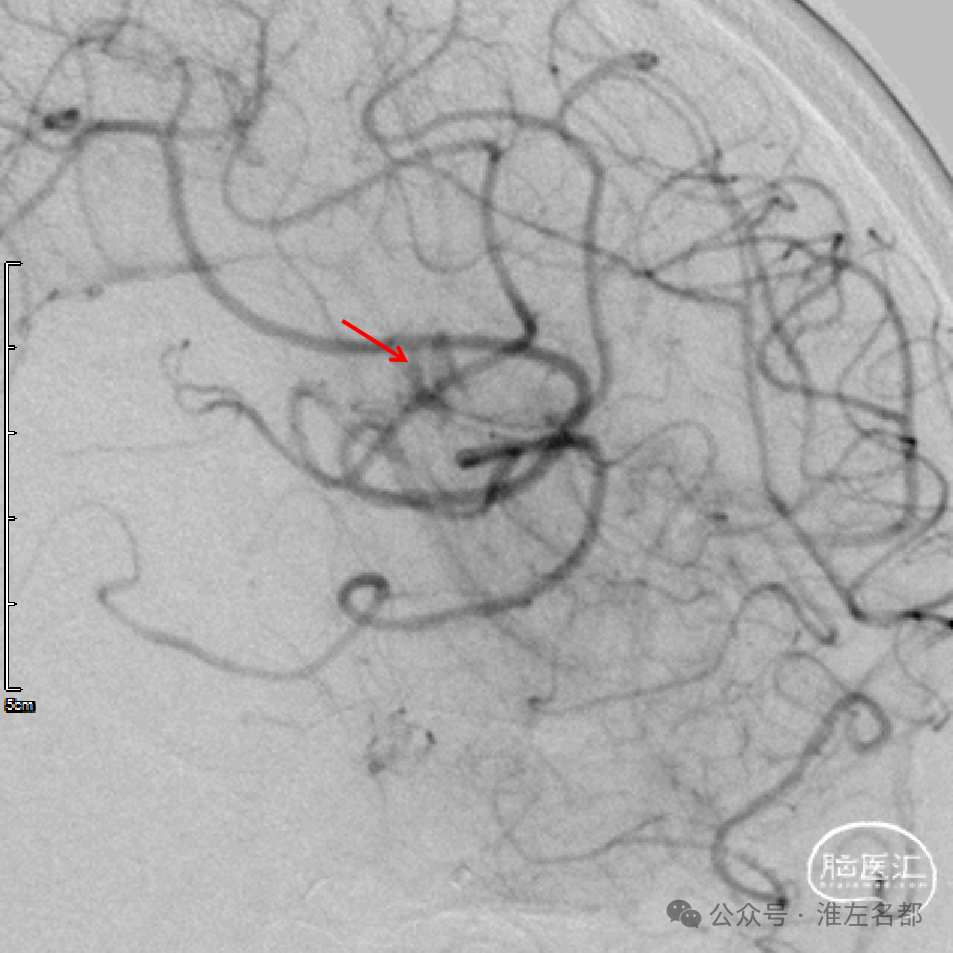

经微导管释放取栓支架(S AB 4*20mm)后造影,前向血流恢复,局部狭窄(红箭)。

回收取栓支架后造影:闭塞再通,右侧A2局部轻微狭窄,但A3-4交界处可见造影剂渗出,提示出血。